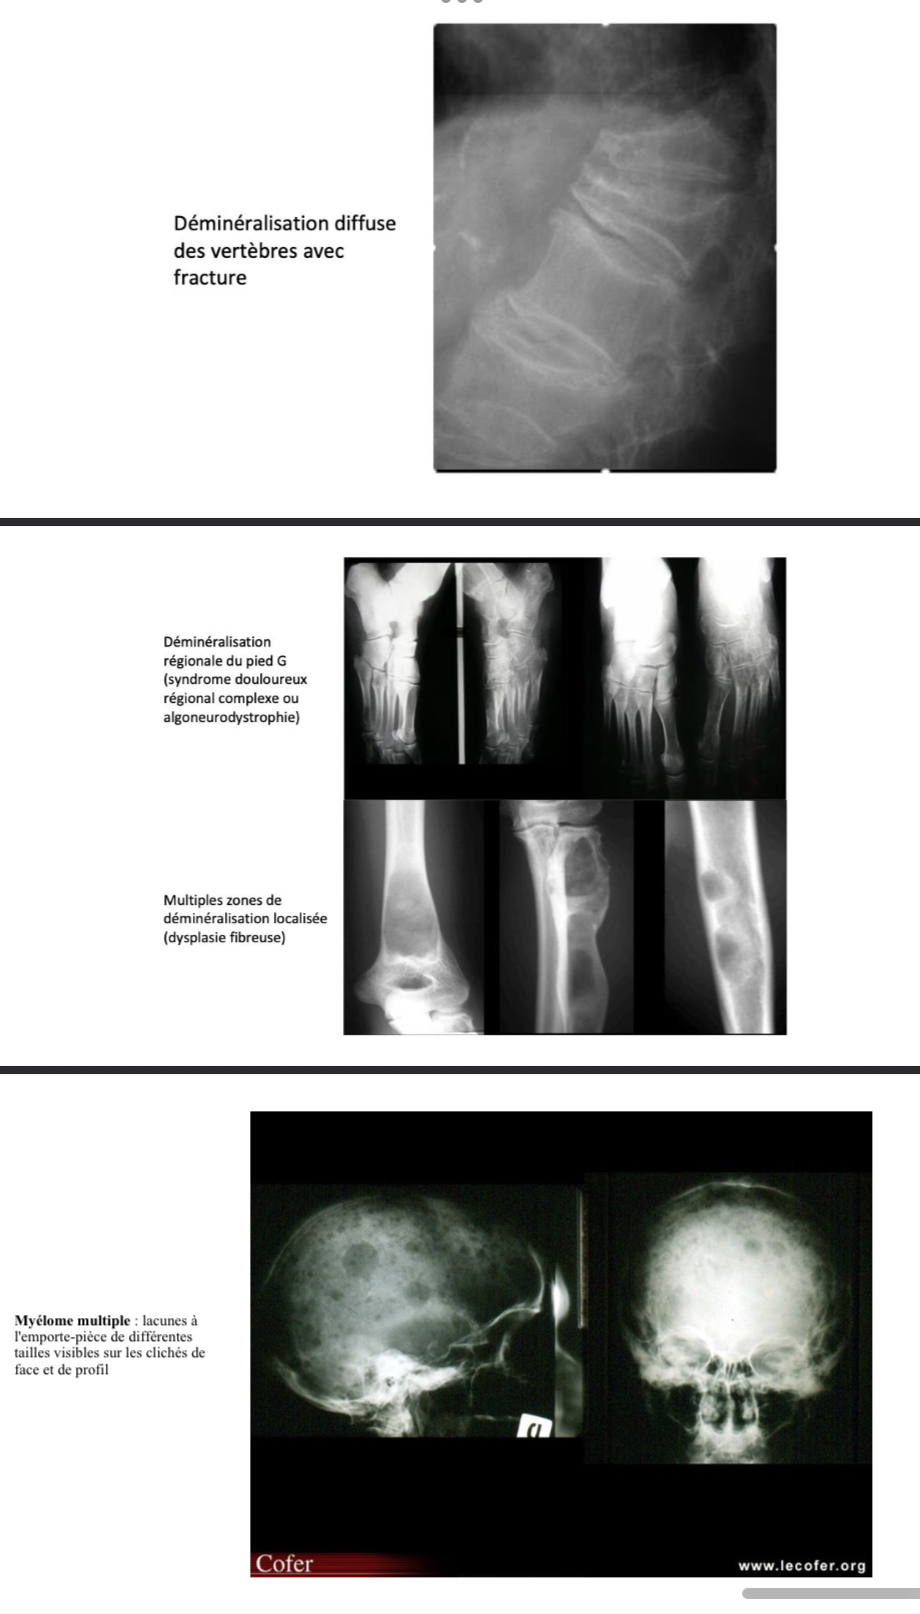

Déminéralisation

= diminution de la densité osseuse

→ diffuse : ostéoporose, hyper parathyroïdie

→ localisée : tumeurs, ostéite, algoneurodystrophine

→ enaires multiples : méta, myélome, dysplasie fibreuse

Fracture vertébrale ostéoporotique

→ localisation < TH6,

→ aspect homogène avec de profil, un aspect cunéiforme (diminution de la haute itérieure du corps vertébral), concave ou biconvexe ou en galette (diminution de hauteurs antérieures, moyennes et postérieures)

→ conservation de la corticale et de l'arc postérieur

Fracture vertébrale maligne

→ localisation > TH6

→ aspect hétérogène, désorganisé, asymétrique de la trame osseuse

→ lyse du mur postérieur et atteinte des parties molles péri-vertébrales

Maladie de Hodgkin

condensation diffuse d’un corps vertébral

Vertèbre « ivoire »